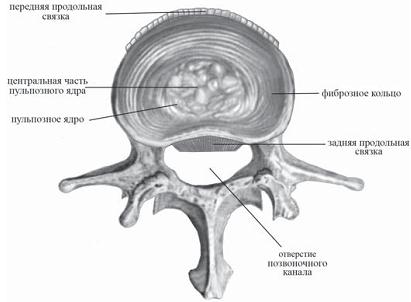

Итак, передняя продольная связка относиться к группе длинных связок позвоночного столба. Это довольно широкий соединительнотканный тяж, который проходит по передней и отчасти по боковым поверхностям тел позвонков и межпозвонковых дисков на всём протяжении позвоночника от нижней поверхности тела затылочной кости, глоточного бугорка и переднего бугорка атланта до первого крестцового позвонка. В верхних отделах связка уже, книзу расширяется. Она тесно прилегает к передней поверхности тел позвонков, прочно фиксирована к надкостнице позвонков и рыхло связана с передней поверхностью межпозвонковых дисков. Это довольно прочное образование, выдерживающее разрыв до 500 кг. Замечу, что при самых тяжких повреждениях позвоночника данная связка почти никогда не рвётся поперечно, а лишь разволокняется продольно. Многие авторы, описывая её назначение, считают, что предназначена она всего лишь для ограничения разгибания позвоночника при движении его кзади. (Читая подобное чуть ли не в каждой книге, невольно с юмором вспоминаешь «закон Вейнера о библиотеках», в котором говорится, что «в библиотеках ты не найдёшь ответов, а только отсылки».) Однако на самом деле, на практике, роль передней продольной связки более значима, чем принято считать. Она участвует в регулировке внутридискового давления. Да и вообще скрывает в себе ещё много познавательного материала для науки. Это уникальная связка, которая требует более тщательного изучения её функций, в том числе со стороны физиков.

Задняя продольная связка, относящаяся к группе длинных связок позвоночного столба, тянется также на всём протяжении позвоночника, но, как указывает её название, по задней (дорсальной) поверхности тел позвонков и межпозвонковых дисков. Данная связка берёт своё начало на задней поверхности тела II шейного позвонка (выше она переходит в покрывную перепонку (мембрану)) и, опускаясь, заканчивается в крестцовом канале. Задняя продольная связка, в отличие от передней, более широкая в верхнем отделе позвоночного столба, чем в нижнем. С телами позвонков она соединяется рыхло, зато прочно сращена с межпозвонковыми дисками, на уровне которых она несколько шире, чем на уровне тел позвонков. У этой связки не менее ответственная роль: она образует переднюю стенку позвоночного канала, препятствует чрезмерному сгибанию позвоночника. И хотя об этой связке известно давно, однако она не спешит расставаться со всеми своими секретами.